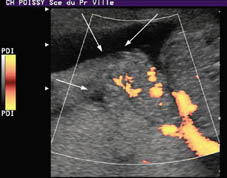

Corte transversal. Embarazo de 21+3 SA. Con Power Energy observamos la vascularización mesentérica de las asas exteriorizadas.